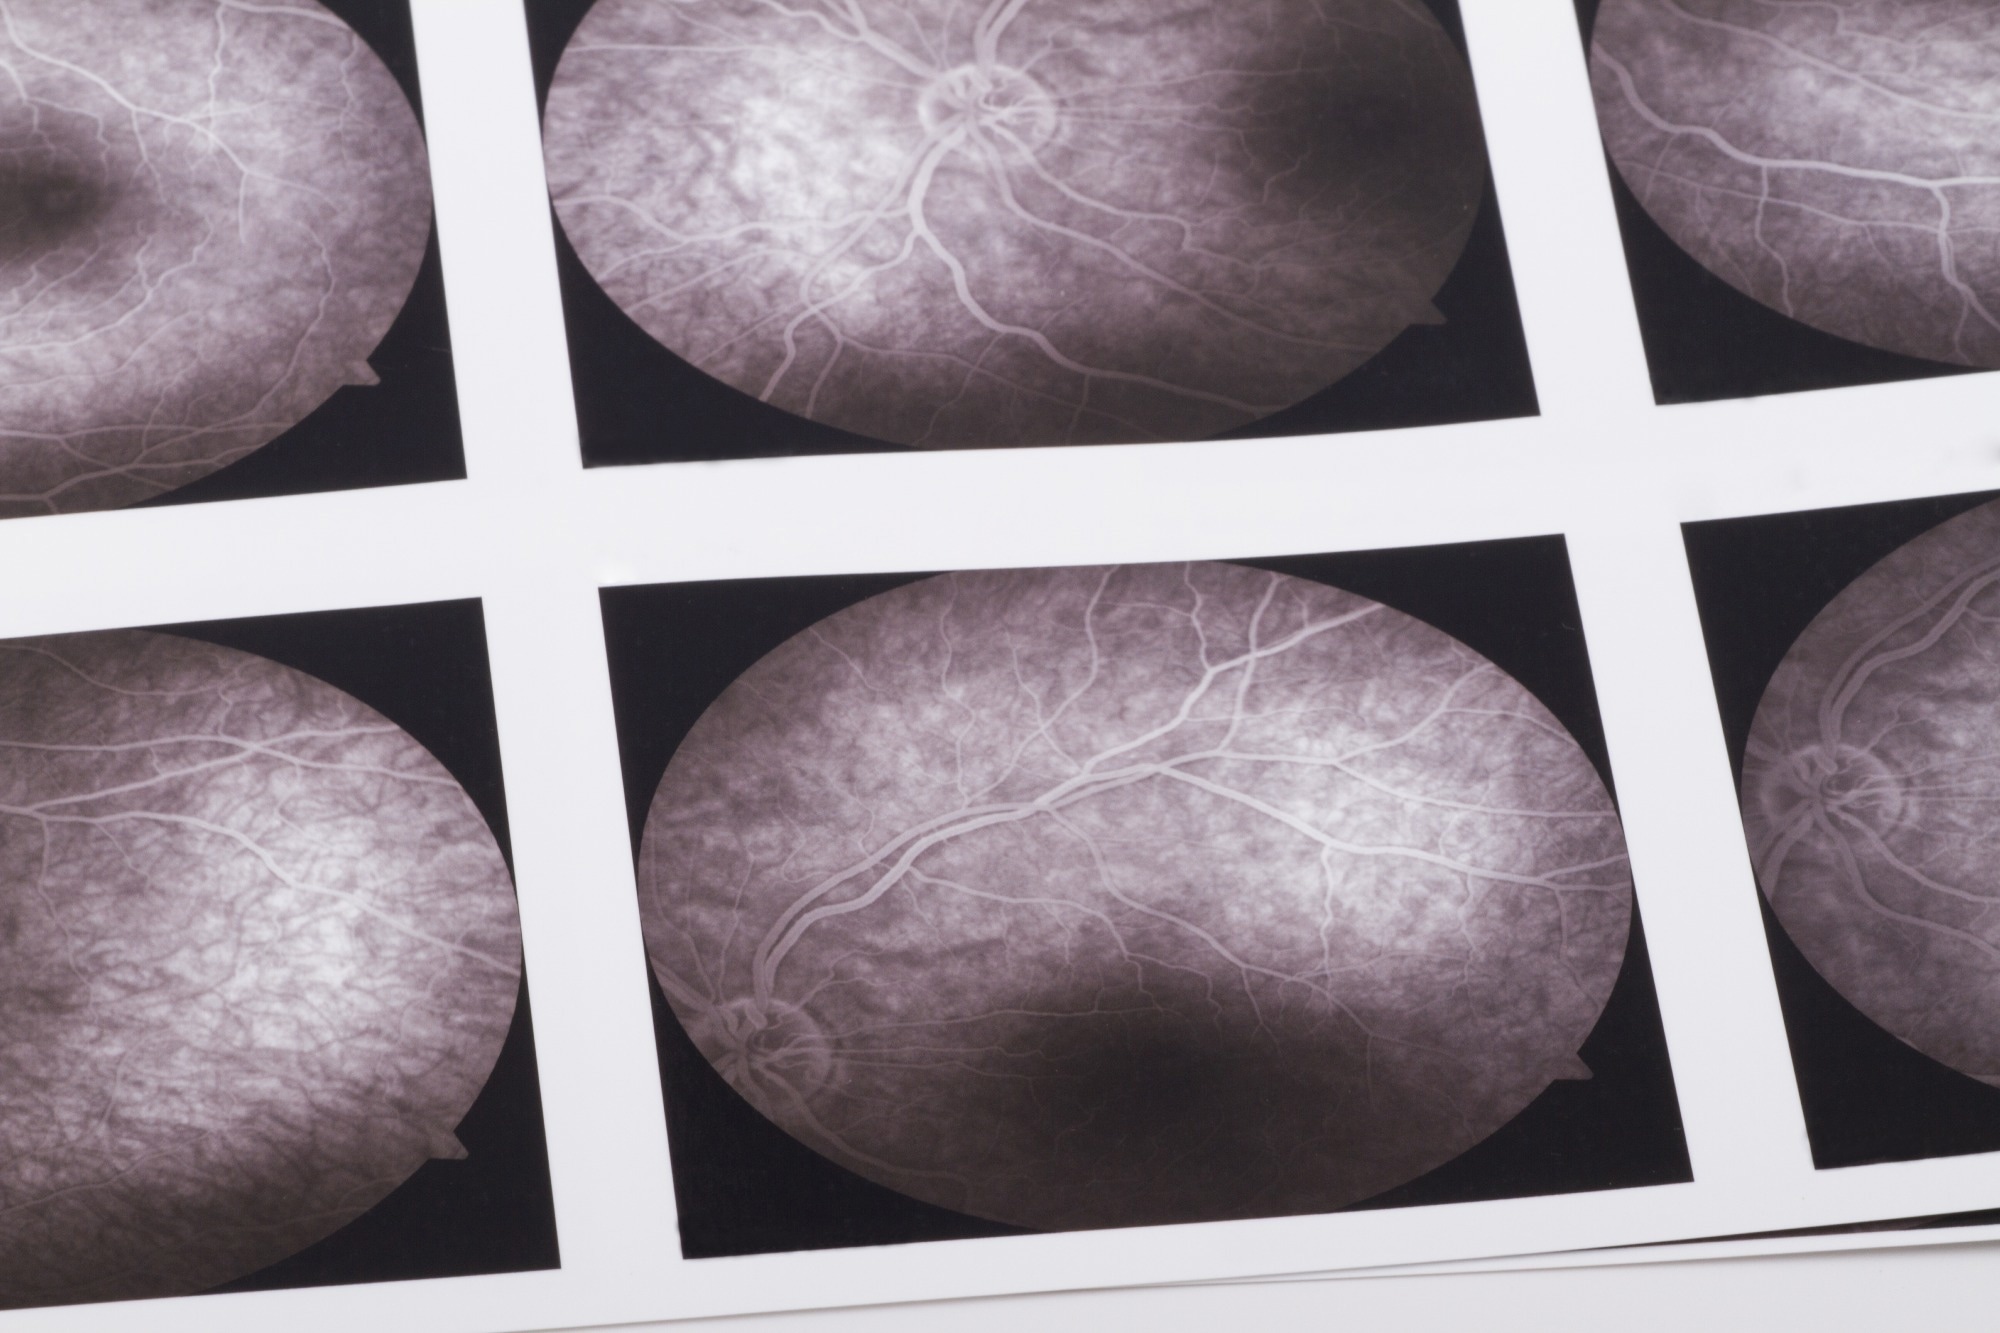

Study: Early detection of dementia through retinal imaging and trustworthy AI. Image Credit: bfk / ShutterstockStudy: Early detection of dementia through retinal imaging and trustworthy AI. Image Credit: bfk / Shutterstock

OCTA is a state-of-the-art imaging technique that allows for rapid and noninvasive imaging of the retinal microvasculature, including even the smallest capillaries with a resolution of 5–6μm. This technology provides detailed insights into the microvascular network and the structure of the foveal avascular zone across different retinal layers, as well as the choroid.

The study data was collected from two primary cohorts—ROMCI (Retinal OCTA-based MCI detection) and ROAD (Retinal OCTA-based EOAD detection)—which comprised retinal images centered on the fovea. The images captured information on the retina's vascular structures, providing the dataset for model training and evaluation.